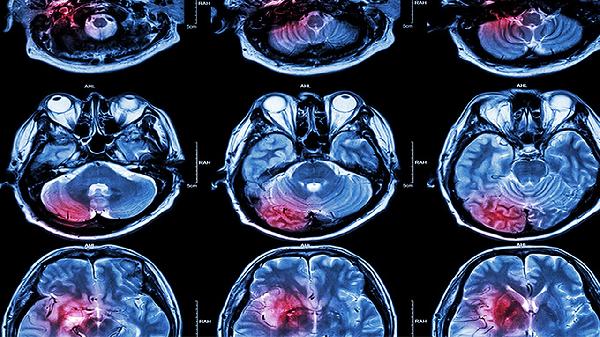

脑血栓康复治疗可遵医嘱使用阿司匹林肠溶片、硫酸氢氯吡格雷片、阿托伐他汀钙片、胞磷胆碱钠胶囊、丁苯酞软胶囊等药物。脑血栓通常由动脉粥样硬化、高血压等因素引起,需结合抗血小板聚集、调脂稳斑、神经保护等综合治疗。